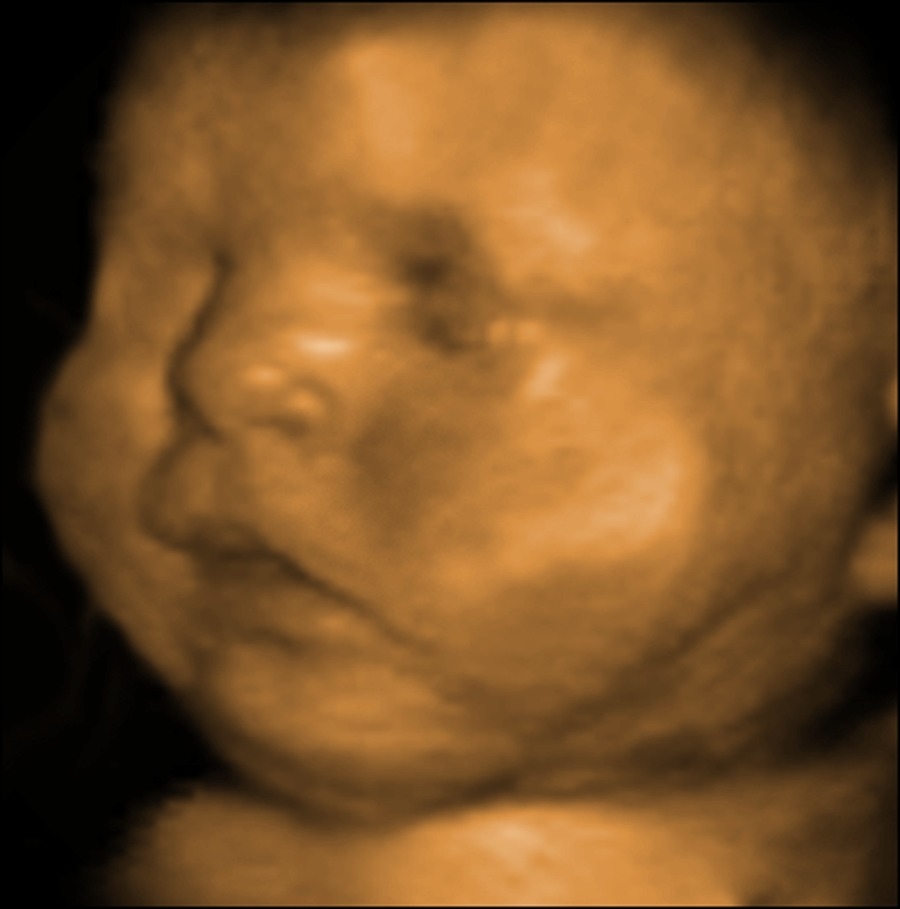

4d Fetal Ultrasound